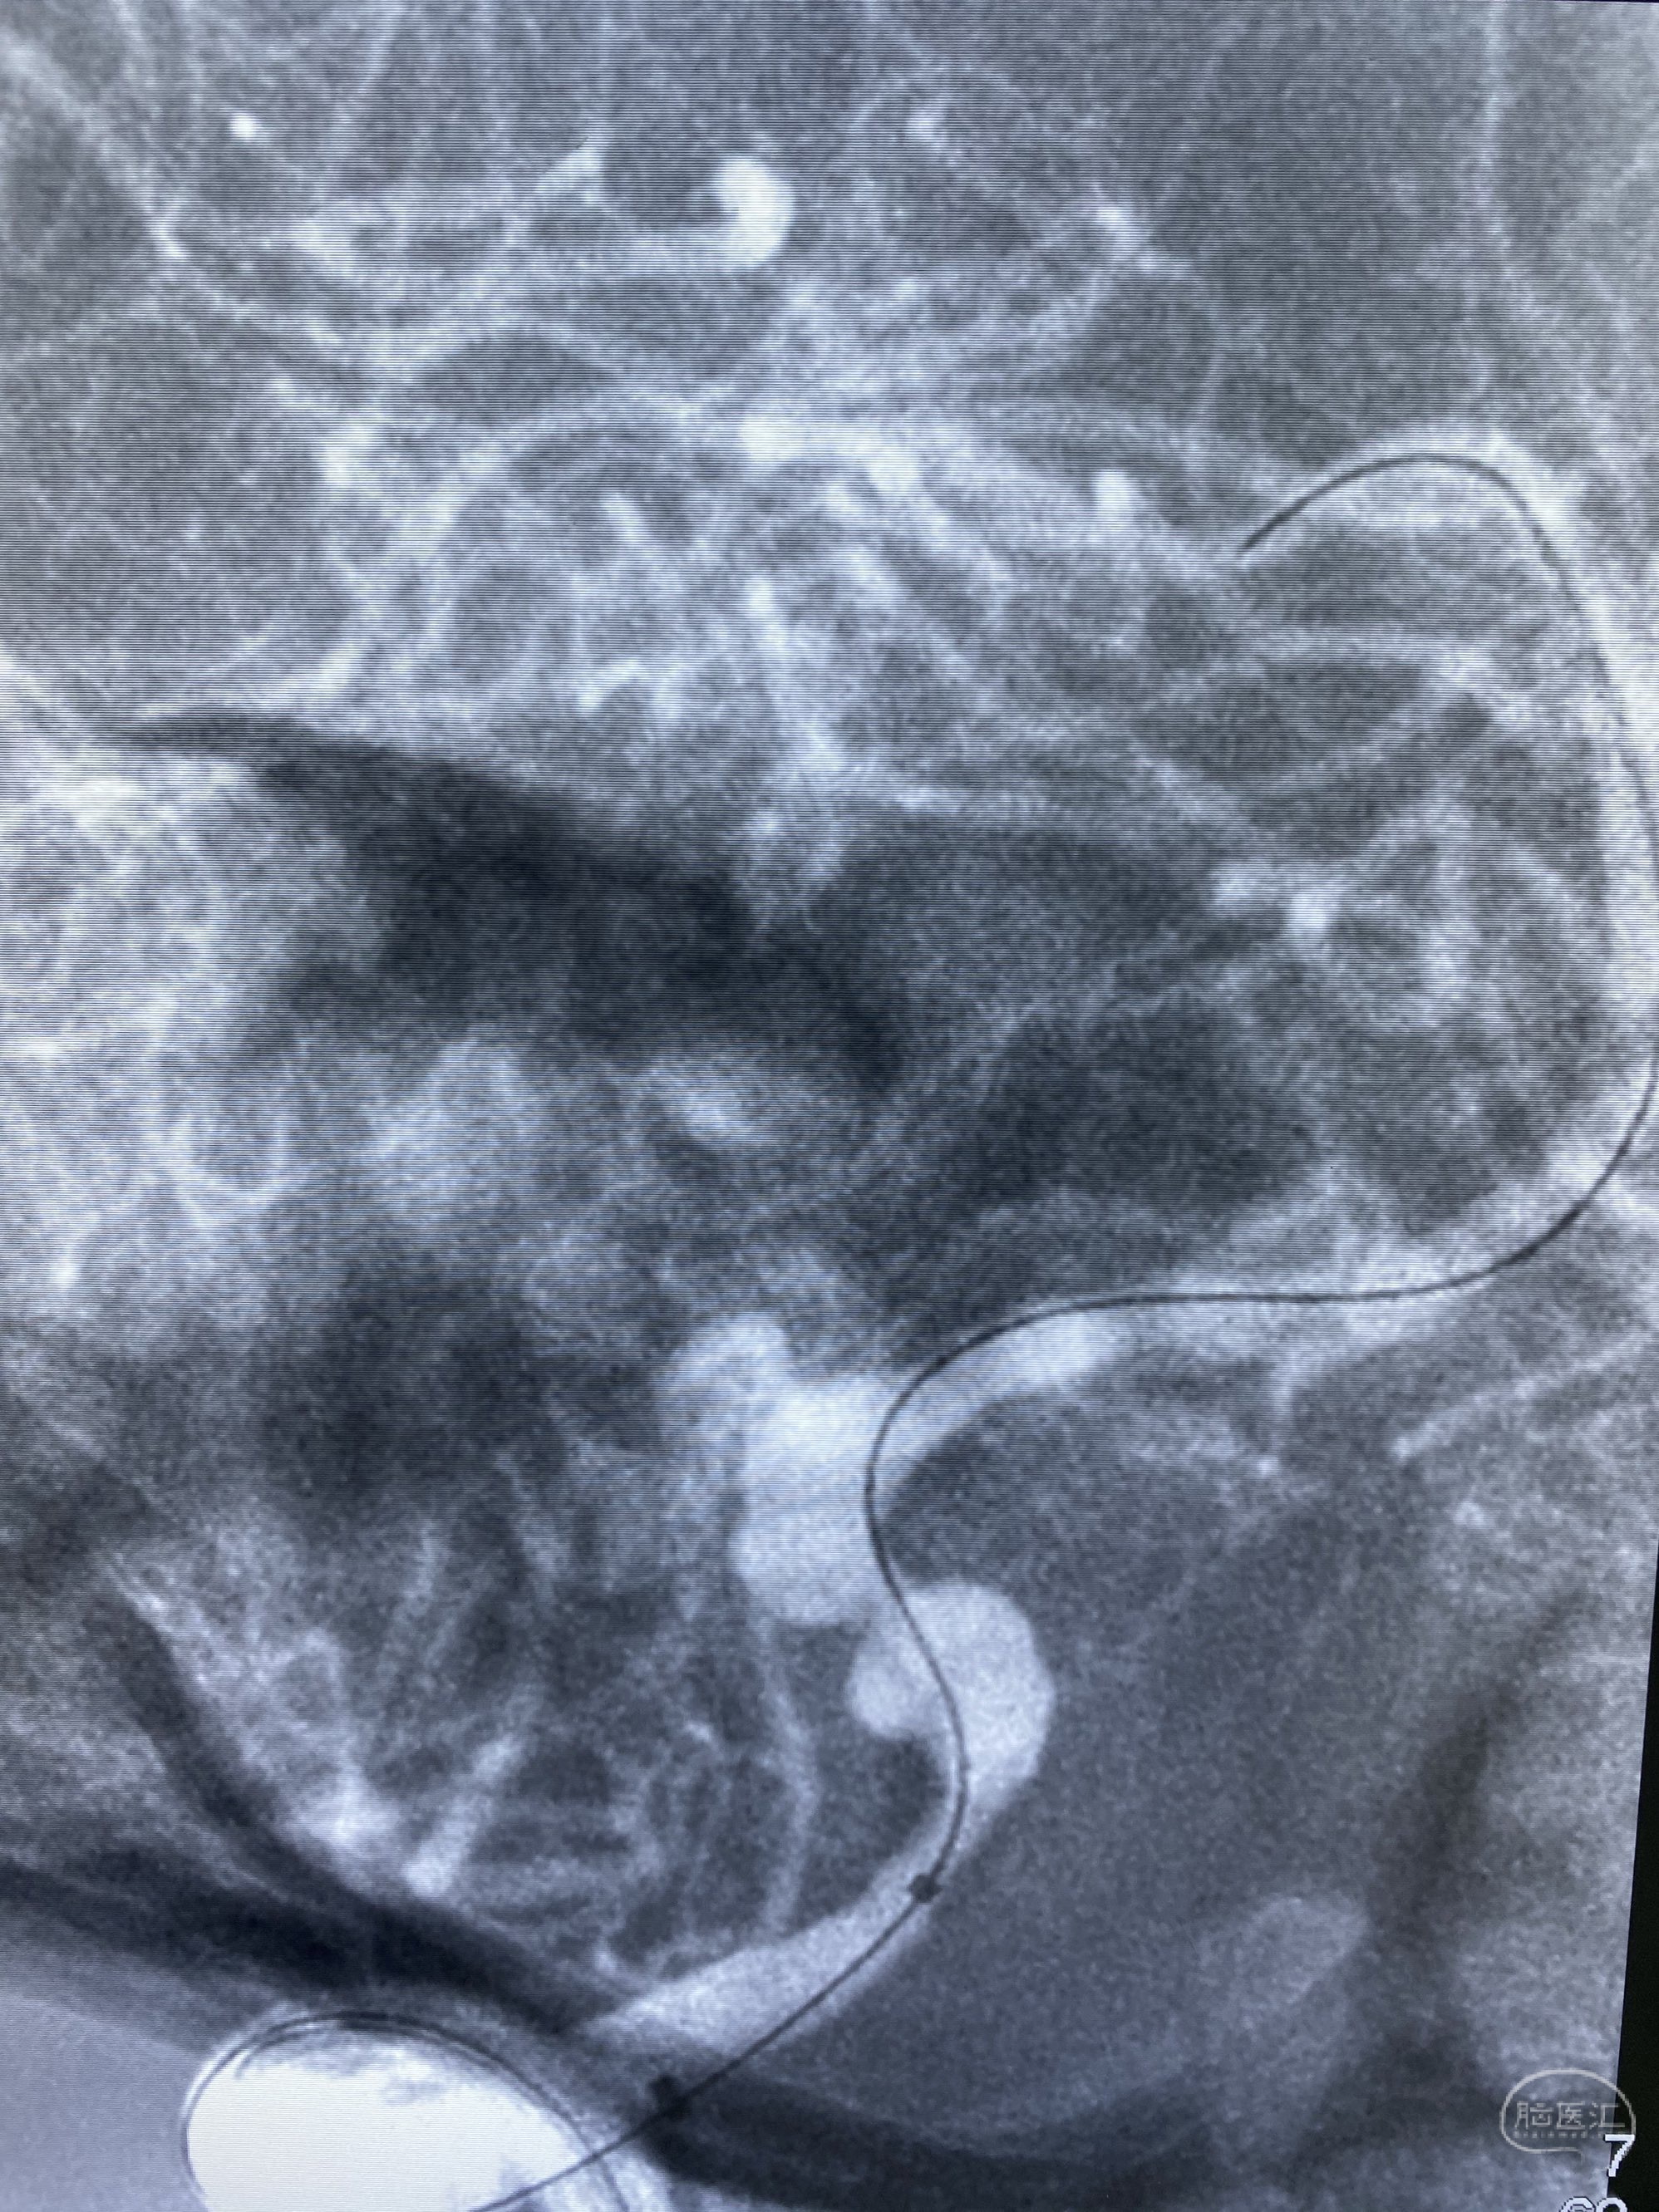

椎动脉颅内段多发夹层动脉瘤伴载瘤动脉狭窄pipeline flex植入

今日手术,TJG,M62Y,一期左侧颈动脉狭窄支架植入,二期椎动脉V4段多发夹层动脉瘤伴狭窄,常规支架辅助栓塞方法复杂又危险,血流导向装置植入快捷又安全。南阳市中心医院神经内科脑血管病介入团队pipeline flexFD植入两人导师资格。